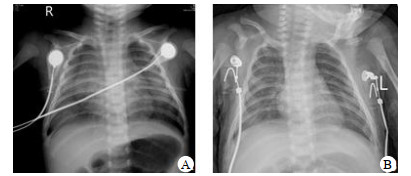

1例1月10 d患儿吸痰时有淡血性分泌物,7例患儿接受了支气管镜检查,2例发现有肺出血,其中1例发现支气管异物(蚕豆)。影像学检查包括胸片与胸部CT,见图 1图 2。NPPE的治疗包括呼吸支持、利尿剂、激素。所有患儿均在3 d内病情好转。

A为入院时胸片提示两肺渗出性病变,透亮度减低; B为2 d后复查胸片明显好转 图 1 1例1月10 d的NPPE患儿胸片